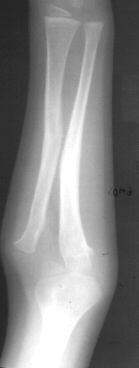

A 4 year and 6 month old male sustained a fall onto an outstretched left arm. He presented to the emergency room with forearm deformity and acute pain(image 1). It was treated with closed reduction and casting (image 2&3). The patient was brought back for another evaluation 10 months after the initial injury(image 4). An x-ray at that time was repeated. On physical examination, he has a prominence over the left radial head. There is full flexion and extension. He has full pronation but lacks 30 degrees of full supination. He is neurovascularly intact(image 5).